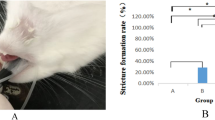

Changes in airway wall stiffness resulting from smooth muscle stimulation were detected by both methods (Fig. 4 and Table 1). Both Caw and the ACI decreased significantly after MCh stimulation. The magnitude of change as measured by both methods was similar. The PTM required to decrease cross-sectional area by 50% was -1.9 ± 0.3 (SE) kPa before and -2.7 ± 0.2 (SE) kPa after MCh stimulation (p< 0.02).

Many investigators have used qualitative means to describe abnormal central airway collapse endoscopically. Presence and severity of tracheomalacia or bronchomalacia have been based on an estimated percent decrease in area of the lumen during exhalation(2, 13, 14). Rozycki et al.(22) assessed the amount of luminal narrowing seen bronchoscopically by calculating cross-sectional area ratios from noncalibrated images of airways at the points of greatest and least narrowing. None of these studies, however, accounted for the infant's degree of expiratory effort and the compressing pressure applied to the airway. In healthy infants with no history of wheeze or airway obstruction, exertional expiratory effort associated with crying or struggling can cause a 50% decrease in the tracheal lumen(32). In our preparation, the amount of pressure required to decrease luminal area by 50% was only 1.9 kPa. Thus, apparently significant central airway collapse seen bronchoscopically may merely be a manifestation of increased compressing pressure.